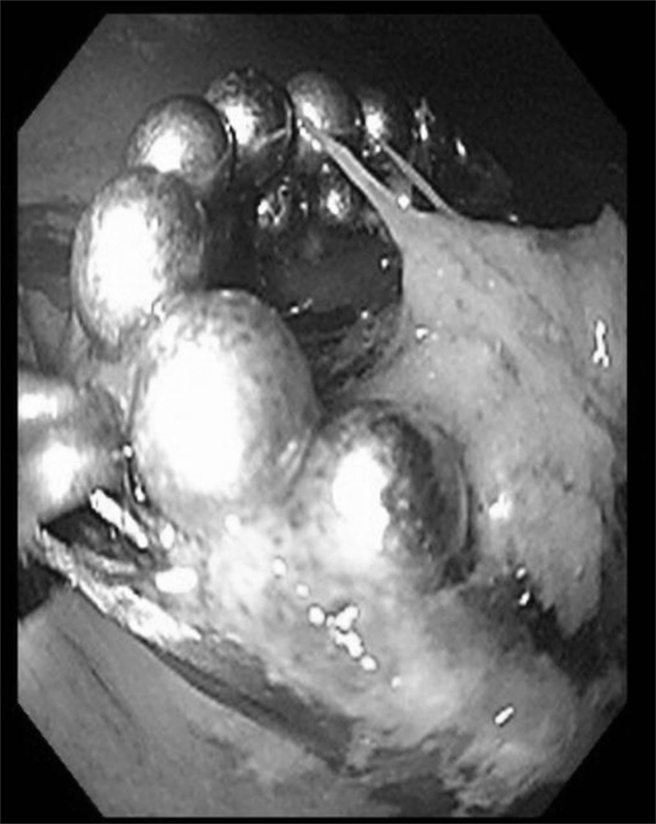

疫情期间,中国医药大学儿童医院急诊部曾收治12岁男童,因把玩益智玩具时误吞32颗磁力球,腹部X光显示胃部有环状磁珠,为避免磁珠进入肠道之后会造成重大併发症及开刀风险,经儿童肠胃道异物处理中心的医护团队紧急採「上消化道内视镜」,并无痛全身麻醉,顺利取出异物,逐渐恢復健康。

中国医药大学儿童医院指出,12岁男童躺在床上把玩磁力球,往空中抛接的霎时间,一不留神竟让整串益智磁珠溜到嘴巴里,惊吓之余顺势吞了下去。随即被送医院急诊,经腹部X光检查后,经採「上消化道内视镜」取出环状如戒指大小的32颗磁力球,男童术后无併发症。